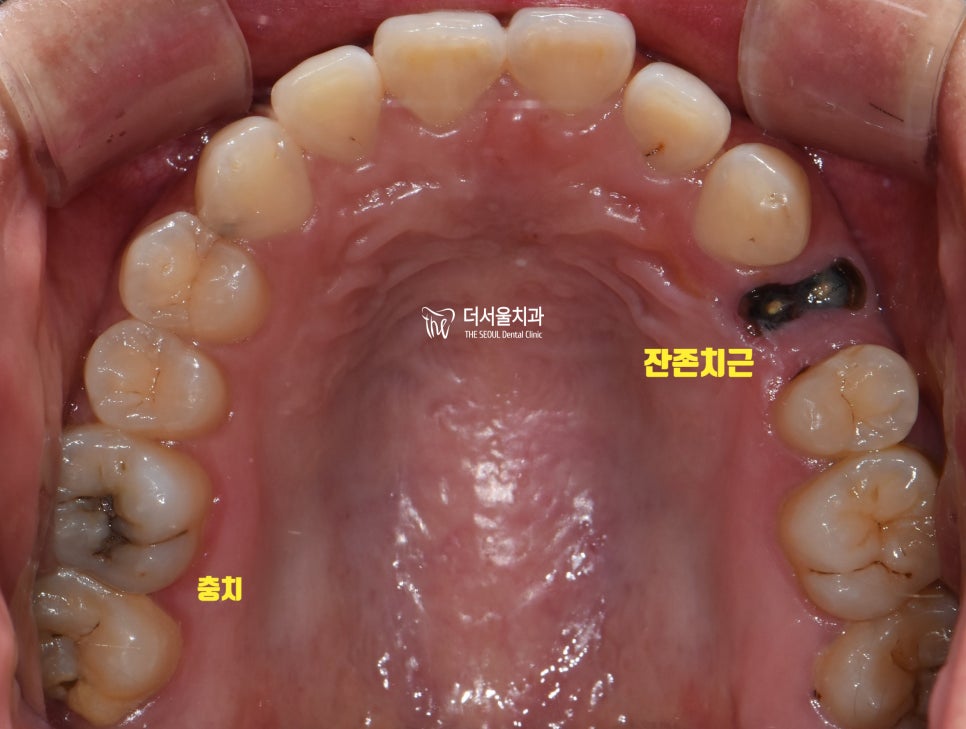

오른쪽은 보시다시피

잔존치근과 충치가 존재했습니다.

살릴 수 있는 곳은 살리는 것이 좋겠죠?

정밀 검진을 진행한 결과,

하악 46번은 잔존치근만 남아있어

이미 살리기엔 늦었다는 판단이 들었으며,

47번 충치 또한 상당 부분 진행되어

이미 신경 부근까지 감염되어 있던 상태였습니다.